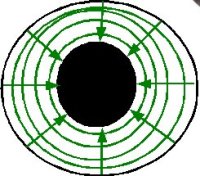

El iris tiene unas fibras radiales, dilatadoras, midriásicas. |

También tiene unas fibras concéntricas, constrictoras, mióticas. |